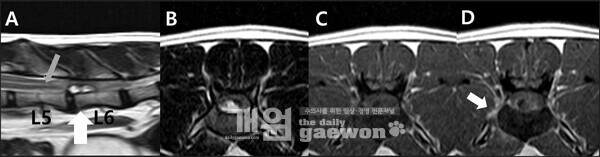

고양이 척수 경막외 섬유성 수막종의 MRI 영상

연구에 따르면, 해당 증례는 MRI 검사에서 추간판 탈출증과 유사한 소견을 보여 감별 진단이 어려웠으나 후궁 절제술과 조직검사를 통해 섬유성 수막종으로 최종 확진됐다. 이러한 경막외 수막종은 매우 드문 형태로, 비전형적 척추 병변의 진단에 중요한 참고 사례가 될 것으로 평가된다.

이번 논문은 요추 추간판 탈출증과 유사한 소견을 보인 고양이의 척수 경막외 수막종 증례를 다룬 연구로 기존에 주로 경막 내에서 발생하는 것으로 알려진 수막종이 경막 외 공간에서 발생한 사례를 영상 진단과 수술, 조직병리학적 분석을 통해 규명한 것이 특징이다.